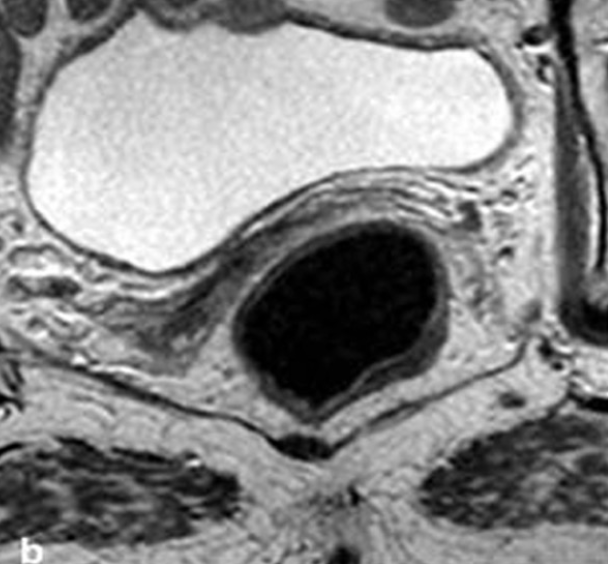

El principal reto para los distintos equipos de coloproctología que están adoptando por primera vez el manejo no operatorio de cáncer de recto o Watch and Wait (WW) es la rigurosidad en el seguimiento a largo plazo y su capacidad de respuesta frente al recrecimiento.

La evidencia demuestra que la incorporación de pacientes a un protocolo de manejo no operatorio está condicionada no sólo al tamaño, estadío y factores de riesgo, sino que también a la altura del tumor para un mejor seguimiento.

El objetivo de este trabajo es establecer estrategias de selección estrictas para el manejo de WW en pacientes con cáncer de recto tratados con (RQT) neoadyuvante que han presentado respuesta clínica completa. Además, discutir la evidencia de los principales estudios de neoadyuvancia con terapia neoadyuvante total (TNT).